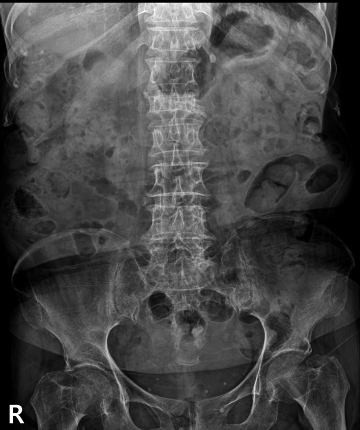

척추골절

척추뼈가 외부 충격으로 인해 찌그러지고 골절되는 질환입니다.

척추뼈의 경우 팔과 다리뼈의 골절과는 다르게 뼈가 찌그러지듯이 납작해지기 때문에 '압박골절'이라 표현합니다. 외형상 변화가 없이 때문에 발생된 후에도 잘 느끼지 못한 채 방치하는 경우가 많습니다.

압박 골절된 척추뼈 (2016.03.18)